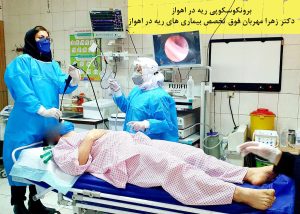

بازتوانی ریوی به عنوان یکی از مهمترین روش های درمانی برای بیماران با مشکلات ریهای شناخته شده است، دکتر زهرا مهربان فوق تخصص بیماری های ریه بزرگسالان و بهترین پزشک و متخصص بازتوانی ریه در اهواز از طریق توانبخشی ریه، به بیمارانی که مشکلاتی مانند بیماری های ریه، آسم، برونشیت و… دارند، کمک می کنند تا بیمار بتواند قدرت و استقامت ریه های خود را افزایش داده و بهبود و درمان شود.

برای این منظور، دکتر زهرا مهربان فوق تخصص بازتوانی ریه در اهواز به بیماران خود در استان خوزستان، ارائه تمرینات و درمان هایی مانند تمرینات تنفسی، تمرینات ورزشی و درمان دارویی تجویز می کنند.

نخستین مرکز بازتوانی ریه در خوزستان در شهر اهواز افتتاح شد. بیمار توسط فوق تخصص ریه معاینه شده و با تشخیص پزشک برای بازتوانی ریوی آماده می شود.

دکتر زهرا مهربان فوق تخصص بیماری های ریوی در اهواز، به بیماران خود ارائه تمرینات و درمان هایی مانند تمرینات تنفسی، تمرینات ورزشی و درمان دارویی را تجویز می کنند و به بیماران خود کمک می کند تا با افزایش قدرت و استقامت ریه های خود، بهبود یابند.